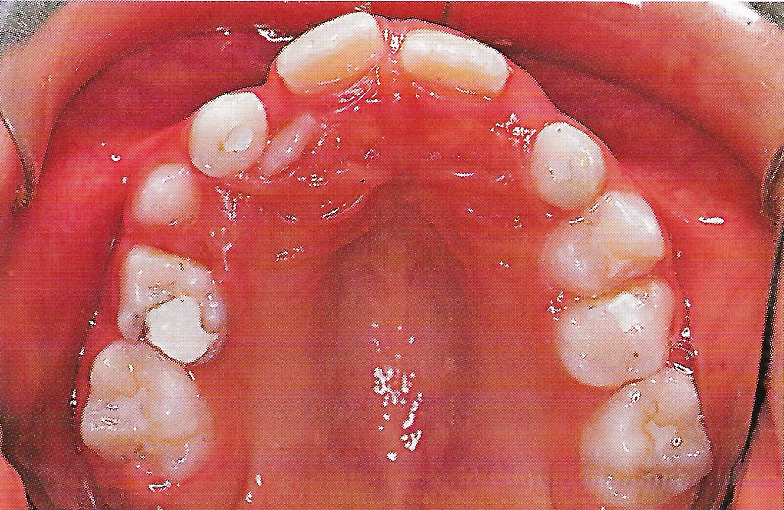

Abb. 1 a bis h Extra- und intraorale Ansicht der Patientin vor Behandlungsbeginn: Kopfbiß beziehungsweise umgekehrter Schneidezahnüberbiß und beidseitiger Kreuzbiß als Folge einer maxillären Hypoplasie sowie hälftenungleicher Mesialbiß infolge mandibulärer Verschiebung nach rechts.

• Ankylose Abb.1e

Diese Patientin war zu Behandlungsbeginn 7 Jahre alt. Sie hatte einen hälftenungleichen Mesialbiß infolge mandibulärer Verschiebung mit Kopfbiß beziehungsweise umgekehrter inzisaler Stufe, rechtsseitigem vollem Kreuzbiß und linksseitigem doppeltem Höckerbiß, maxillärer Kompression sowie Platzmangel in beiden Kiefern (Abb. 1 a bis h). Die kephalometrische Analyse ergab eine progene Kieferlagebeziehung, bedingt durch eine unterentwickelte Maxilla bei vertikalem Gesichtsschädelaufbau.